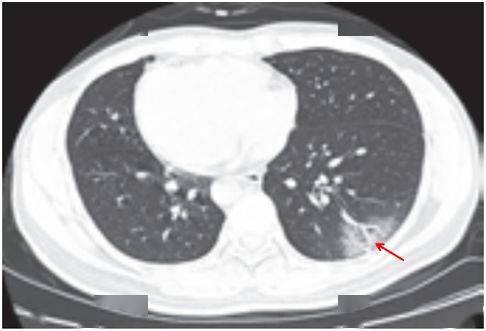

病灶以 肺外围背侧为主,以两肺下叶为著,与胸膜常紧贴,提示新冠肺炎病变多首先侵犯皮层肺组织的细支气管及肺泡上皮, 病灶分布逐步从外周向中央扩展(图 2-1)

图2-1 早期病灶多数分布贴近胸膜( 共4张 )

(三)病灶密度

绝大多数案例出现磨玻璃病灶,最低测得 CT 值约为 - 600Hu(图 2-3),病灶内血管穿行可清晰显示;部分案例磨玻璃病灶与实性病灶共存

根据既往严重急性呼吸综合征(SARS)病理学机制,提示此为肺泡间隔毛细血管扩张充血、肺泡腔内液体渗出和小叶间隔间质水肿

图 2-3早期绝大多数病灶表现为磨玻璃密度( 共4张 )